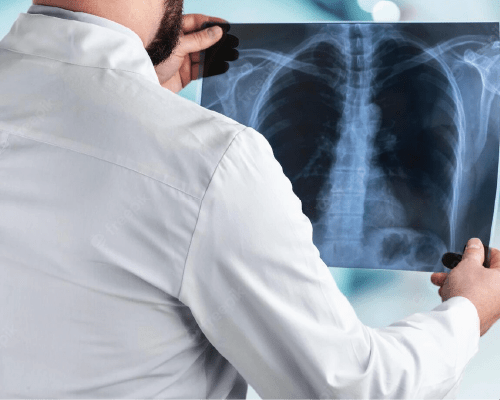

Digital radiography is a form of X-ray imaging , where digital X-ray sensors are used instead of traditional photographic film. Advantages include time efficiency through bypassing chemical processing and the ability to digitally transfer and enhance images. Also, less can be used to produce an image of similar contrast to conventional radiography.

Instead of X-ray film, digital radiography uses a digital image capture device. This gives advantages of immediate image preview and availability; elimination of costly film processing steps; a wider dynamic range, which makes it more forgiving for over- and under-exposure; as well as the ability to apply special image processing techniques that enhance overall display quality of the image.